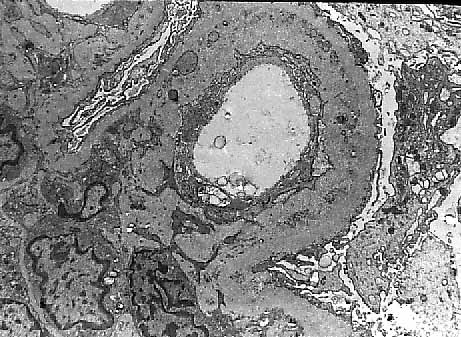

El criterio histológico mas importante es el engrosamiento de la membrana basal glomerular con presencia de dobles contornos, ensanchamiento subendotelial, característica muy frecuente en el estudio ultraestructural (fig 9 y 10). En el estudio de inmunofluorescencia son muy frecuentes los depósitos exclusivamente de IgM (21,31).

| Figura 10. Glomerulopatía del trasplante. Estudio ultraestructural con importante engrosamiento de Membrana basal y glomerular. |